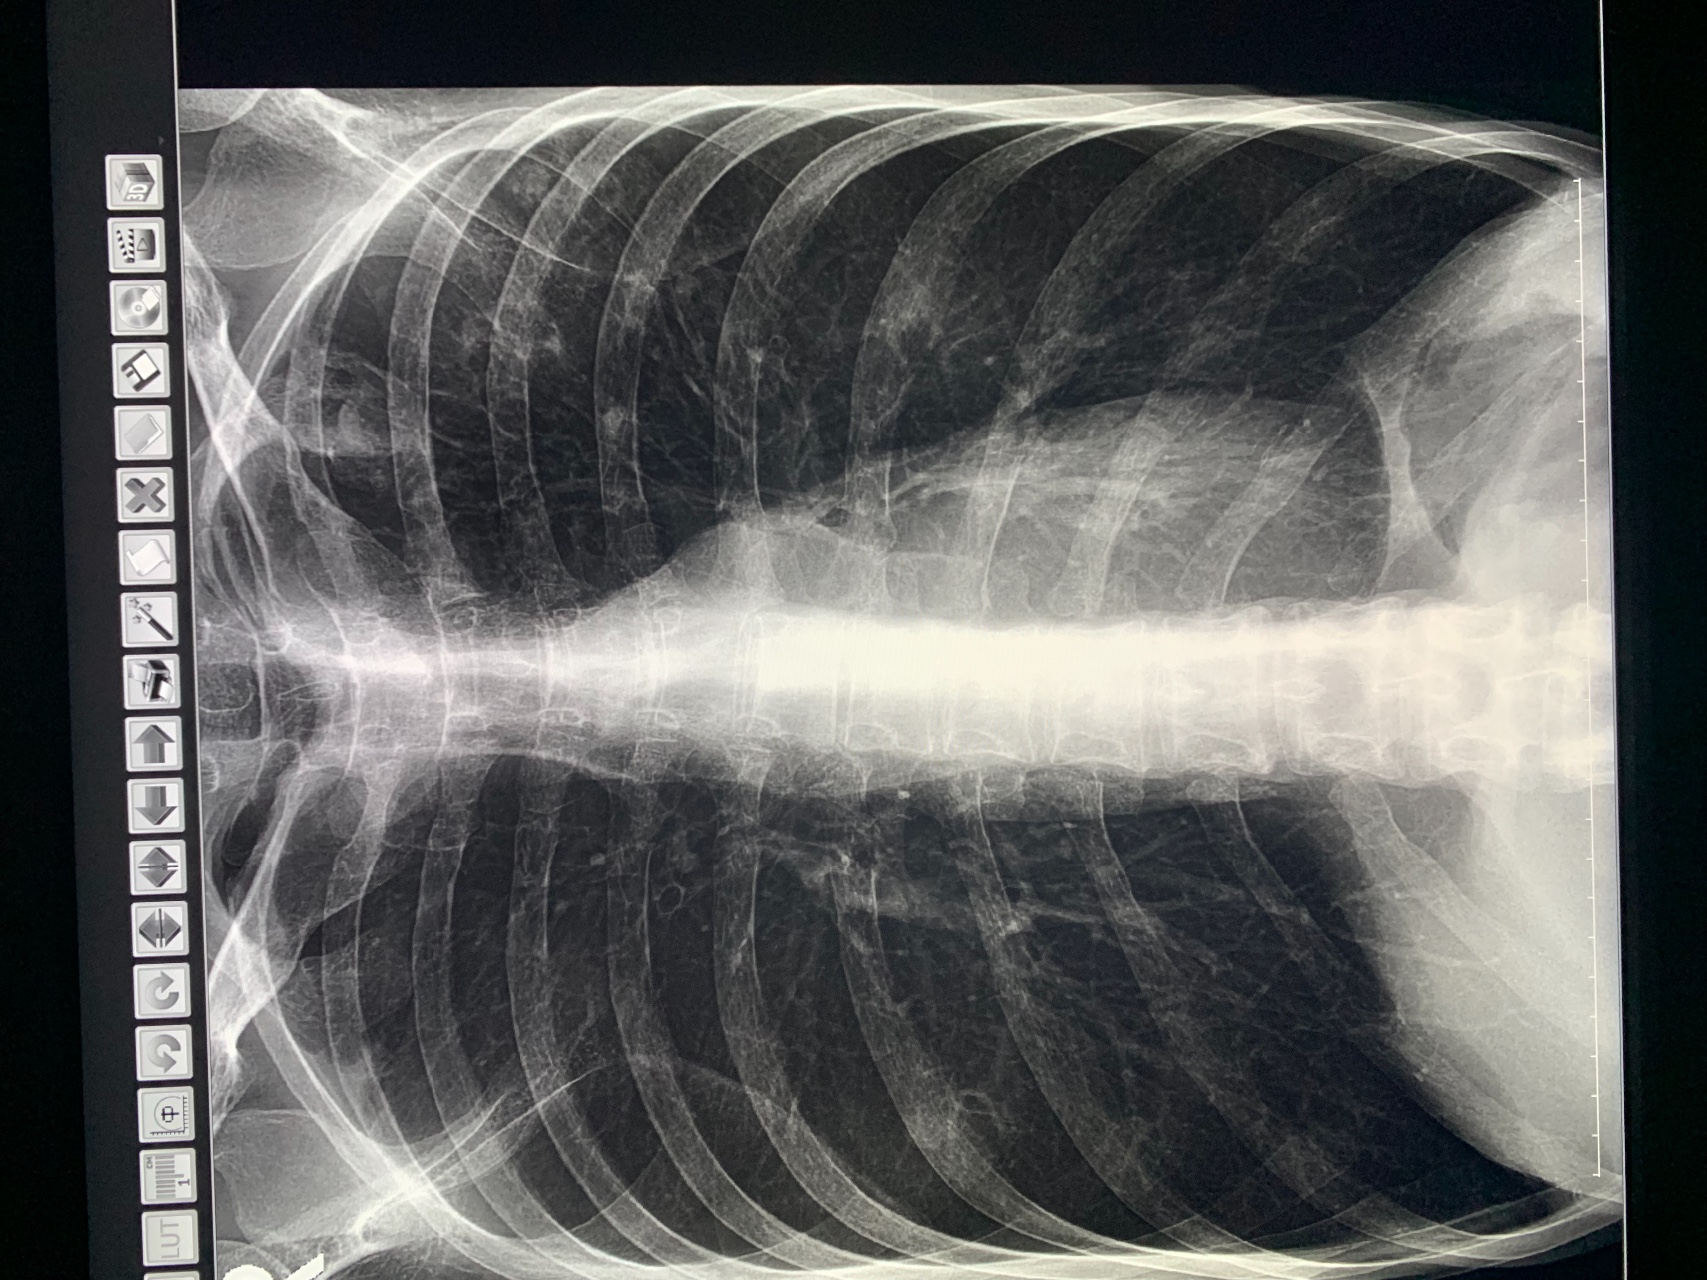

Рентген здоровых легких: примеры снимков и советы

Раздел: Сокровищница опыта